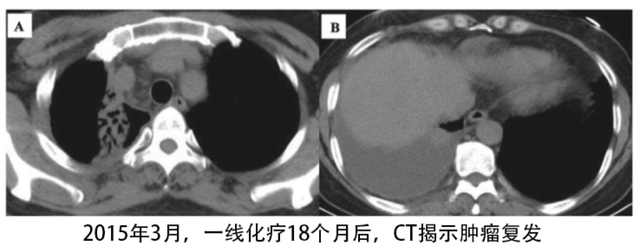

2015年3月,距离一线化疗之后的18个月,患者主诉右胸疼痛不适,CT影像学显示肿瘤复发。

对患者重新取样再次进行分子检测,免疫组化(Ventana)揭示有ALK基因融合突变,且通过RT-PCR再次确认了ALK基因融合突变。奇怪的是再次做EGFR基因检测发现存在EGFR基因的19外显子缺失突变,且EGFR还存在过度表达。